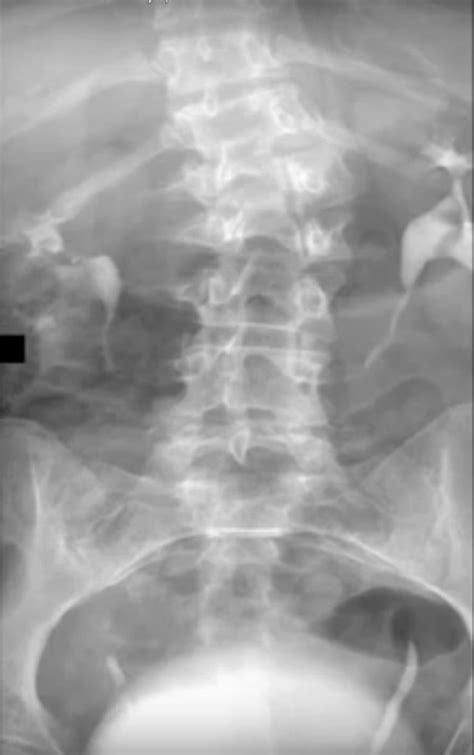

Frida Kahlo Bus Accident, " El Acidente" (The Accident) | El Acidente" ( The ..., On september 17, 1925, kahlo was riding in a bus when the vehicle collided with a trolley car.. She is pictured on the far right. Born outside mexico city in 1907, frida kahlo. When she was able to get up and move around again, she was limping — her right foot and leg had been damaged by the disease, according to biography. Frida painted her recollection of the last moments aboard the bus before the terrible accident that robbed her of her health. She suffered serious injuries in the accident, including a broken spinal column, a broken collarbone, broken ribs, a broken pelvis, eleven fractures in her right leg, a crushed and dislocated right foot, and a dislocated shoulder.

Apr 06, 2020 · frida kahlo, born in 1907 in mexico, was one of the lucky ones: She exhibited her paintings in paris and mexico before her death in 1954. She was about six years old when she contracted polio, forcing her to stay in bed for around nine months as she recovered. Frida painted her recollection of the last moments aboard the bus before the terrible accident that robbed her of her health. What accident was frida in? Kahlo was no stranger to pain and suffering. She suffered serious injuries in the accident, including a broken spinal column, a broken collarbone, broken ribs, a broken pelvis, eleven fractures in her right leg, a crushed and dislocated right foot, and a dislocated shoulder. Notice that she is not dressed in traditional mexican costume. On september 17, 1925, kahlo was riding in a bus when the vehicle collided with a trolley car. Born outside mexico city in 1907, frida kahlo. May 26, 2009 · "the bus," by frida kahlo (1929). On 17 september 1925 frida was on a bus to coyoacán, accompanied by her boyfriend alejandro gómez arias. Accident, september 17, 1926 (1926) by frida kahlomuseo dolores olmedo on 17 september 1925 frida was riding a bus to coyoacán, back to her house after preparatory school.

On 17 september 1925 frida was on a bus to coyoacán, accompanied by her boyfriend alejandro gómez arias. Apr 06, 2020 · frida kahlo, born in 1907 in mexico, was one of the lucky ones: She is pictured on the far right. On september 17, 1925, kahlo was riding in a bus when the vehicle collided with a trolley car. She suffered serious injuries in the accident, including a broken spinal column, a broken collarbone, broken ribs, a broken pelvis, eleven fractures in her right leg, a crushed and dislocated right foot, and a dislocated shoulder.